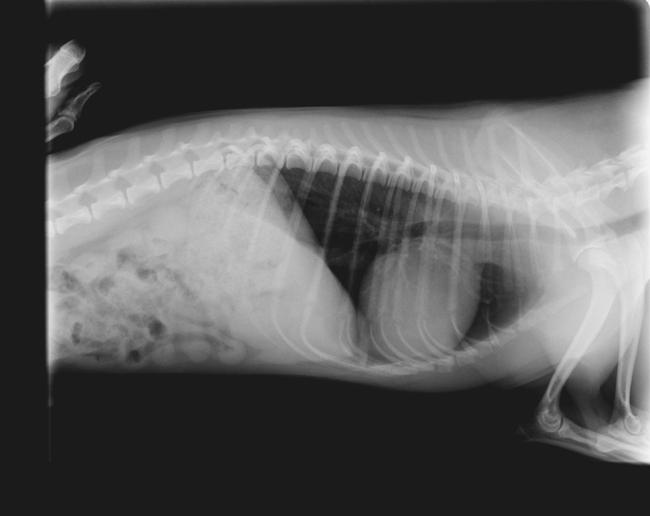

Hier de foto's van zijn ribben (3 maand geleden)

Op de eerste foto is de breuk duidelijk te zien... ( links vanonder)

Wat een mooie kwaliteit röntgen foto! Je ziet zo het hart, longen, lever?, maag? zitten! En helaas ook die breuk, maar goed daar liet je de foto voor nemen.

Ja de fotos zijn via mail doorgestuurd dus er is toch een beetje kwaliteit weg..Op eerste zicht leek max ook niets te hebben... maar de DA voelde iets raar bij zijn ribben ..

Ik wilde zowizo foto's laten maken voor de zekerheid en ja toen zag ik duidelijk die breuk